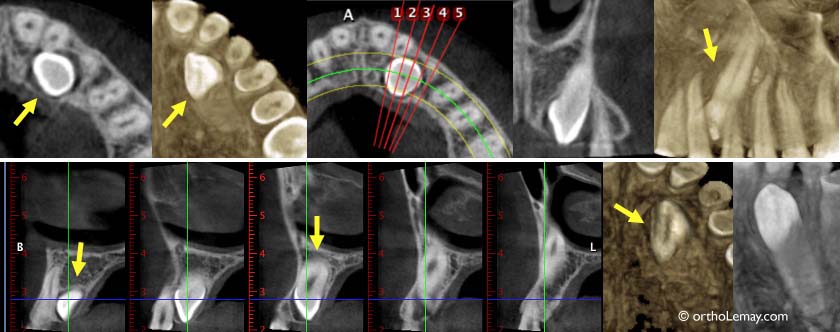

Exemple de clichés obtenus à l’aide d’une tomodensitométrie volumique tri-dimensionnelle pour localiser une canine incluse palatine (indiquée par les flèches). Ceci permet de s’assurer que la racine de la latérale n’est pas affectée par la dent incluse.